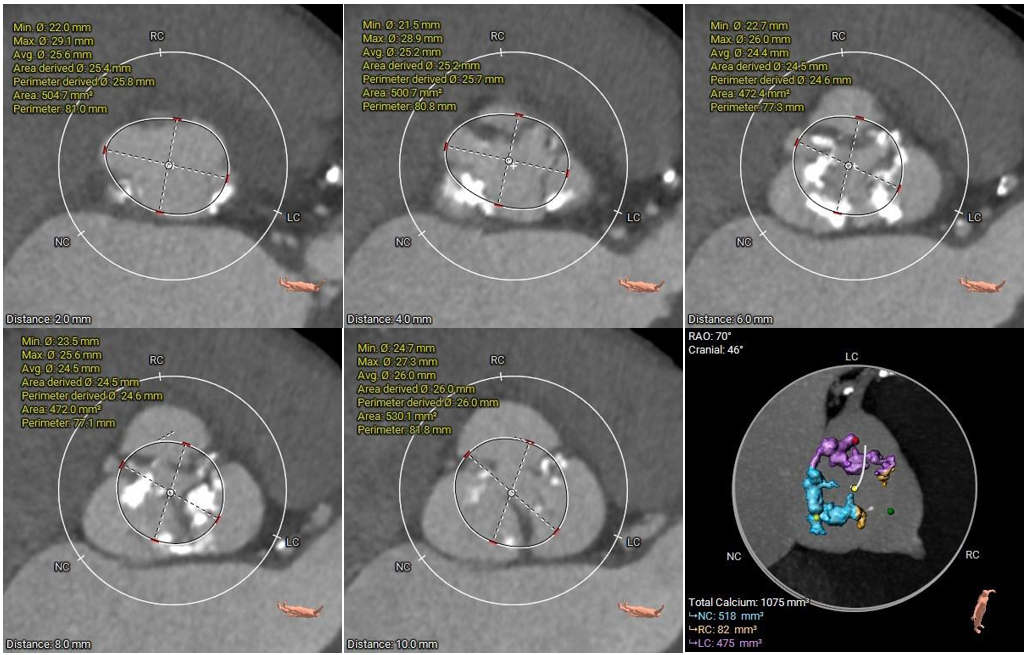

瓣上结构测量及钙化积分

冠脉阻挡风险、横位心及左室大小评估

• 三叶式主动脉瓣,瓣叶增厚伴重度钙化,钙化积分1075mm³,钙化分布相对较均匀,瓣膜锚定难度尚可,瓣膜释放后可能出现形态受限及瓣周漏情况;

• 左右冠开口高度尚可,切线位测量未见冗长瓣叶,预估冠脉堵塞风险不高;